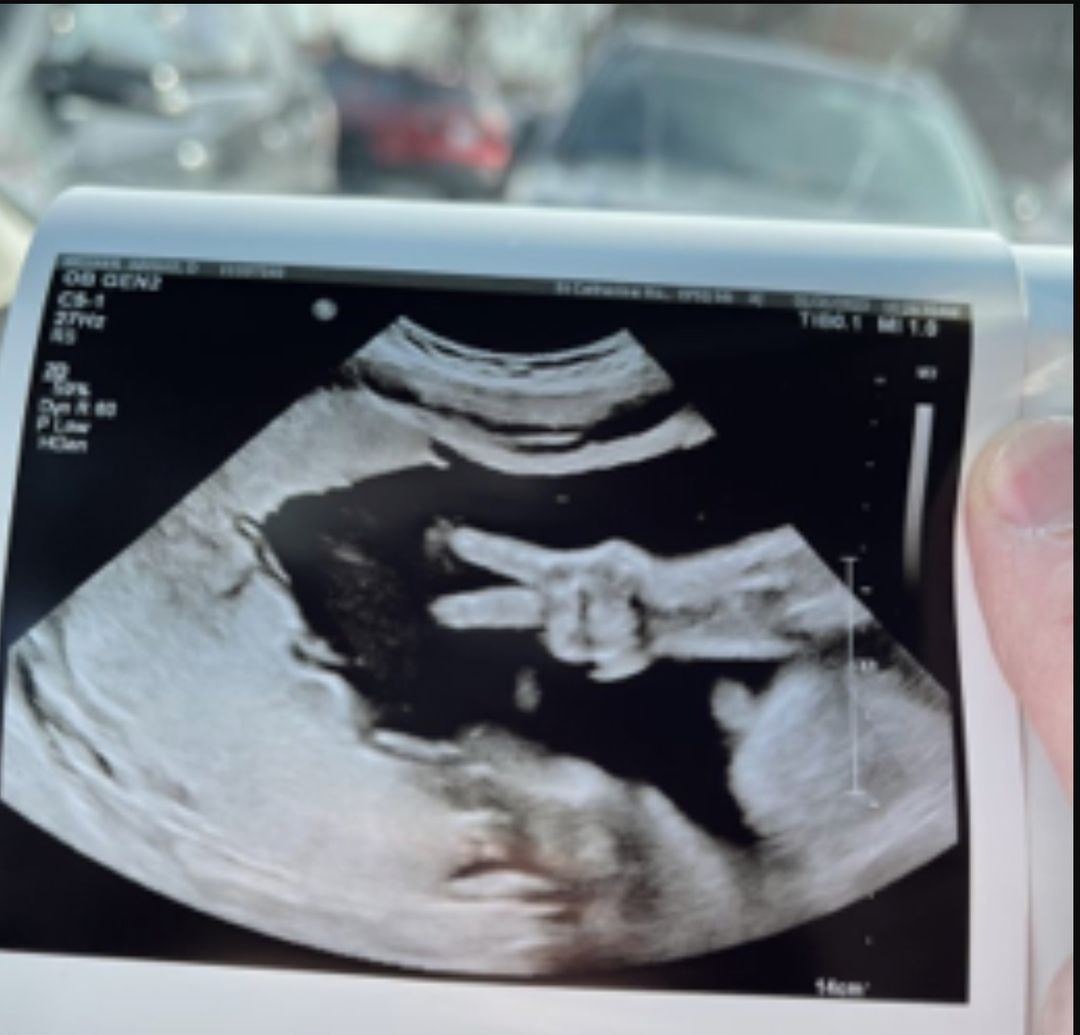

【產前檢查】準媽媽產檢驚見BB鬼馬比「V手勢」打招呼 醫護人員大笑:以前從未見過!

準爸爸媽媽最期待的莫過於做產檢照超聲波時與寶寶的第一次見面,美國有一對夫妻在照超聲波時,寶寶突然和他們比「Yeah手勢」打招呼,令2夫妻以及在場的醫護人員都感到相當驚喜!醫護人員表示,這是多年來第一次見到,「這是非常獨一無二的!」

寶寶突然比「Yeah手勢」令人感到驚喜

綜合外媒報導,來自美國印第安納州的準媽媽Abigail Weener,和老公Kyle Weener育有2名孩子,如今又即將迎接第3個孩子。準媽媽Abigail Weener目前已懷孕32週,距多數產婦的預產期只相差8週。她在2月1日前往聖凱瑟琳醫院(St. Catherine Hospital)做例行產檢,當醫生拿著儀器對著她的肚子照超聲波時,胎兒卻突然在肚子裡有了反應,讓全場都驚呆了,老公Kyle Weener表示:「技術人員看著肚子,觀察寶寶,突然間,寶寶的2根手指頭就這樣豎了起來。」寶寶突然豎起食指和中指,看起來就像在與爸爸媽媽比「Yeah手勢」。

醫生見狀便馬上轉頭看向夫妻2人,接著全場便開始大笑,似乎被寶寶的舉動給萌翻了,老公Kyle表示:「職員說他們以前從未見過這樣的事情,這件事是獨一無二的。」

網民:她會是一個很酷的孩子!

超聲波拍到寶寶比出的「Yeah手勢」十分清晰,令Kyle忍不住把照片分享至社交平台Facebook,並寫道:「Ellie過上最好的生活!平安!」(Ellie’s living her best life!Peace out!)不少網民看了照片後都感到非常神奇,紛紛留言表示:「她會是一個很酷的孩子!我等不及見到她」、「等不及她出生了!」、「太特別了」、「她將成為一個有趣的小女孩」、「哇,她說這裡一切都好,一個幸福舒適的子宮可以繼續發育」。